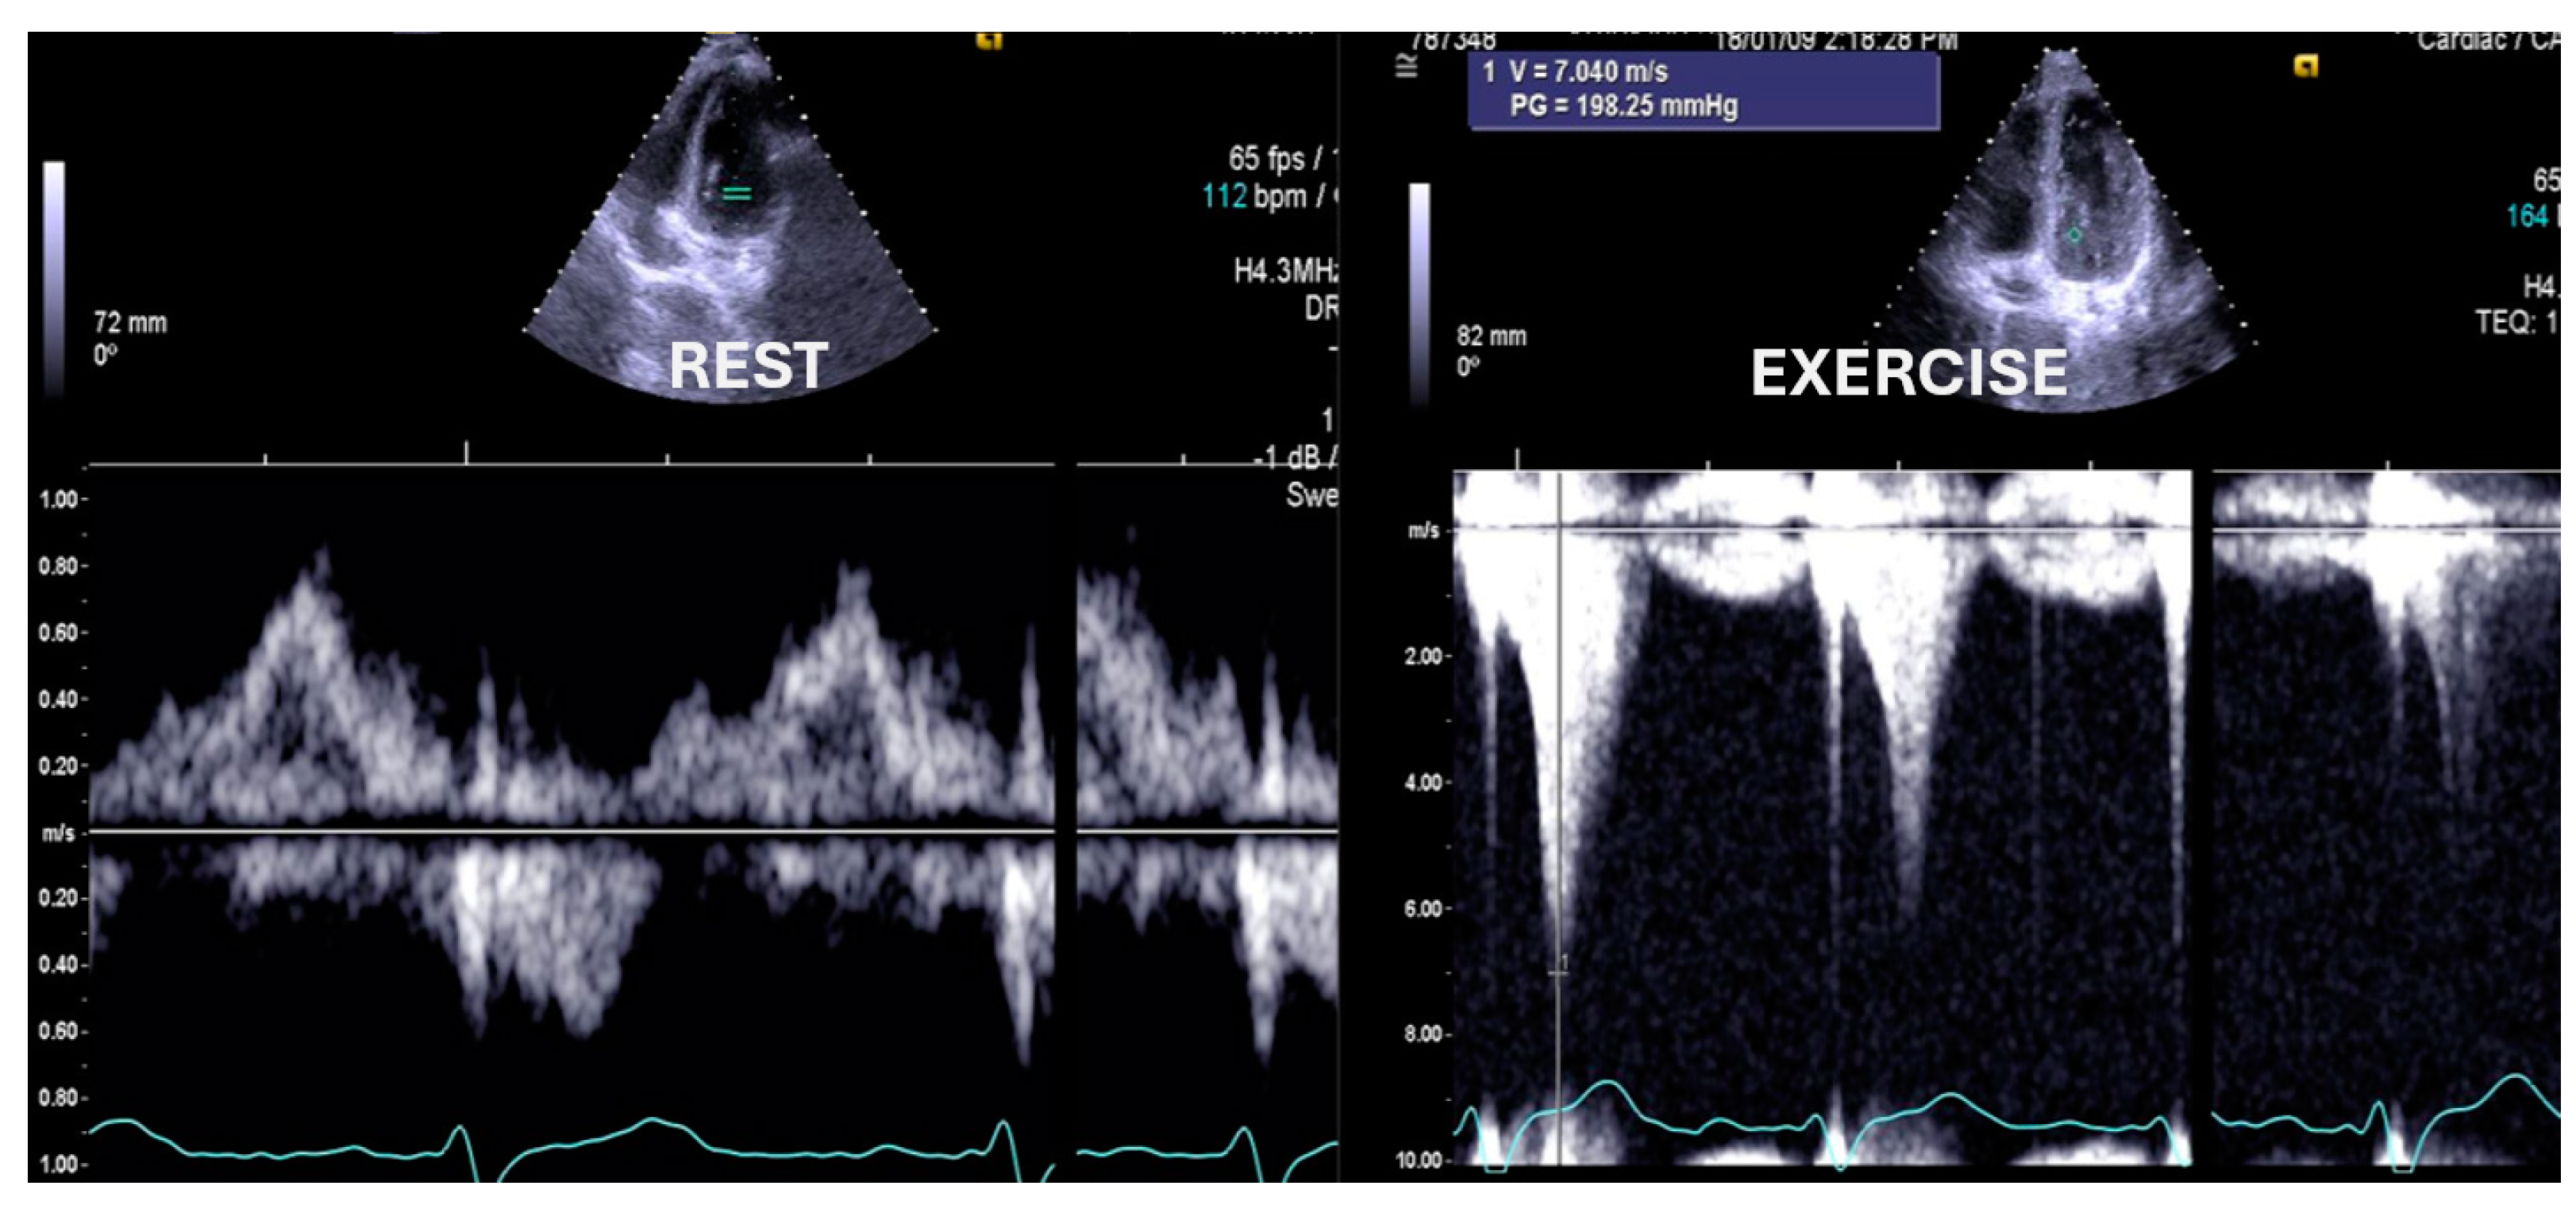

- Cotrim, C.; Palinkas, E.D.; Cotrim, N. The Importance of Left Ventricular Outflow Tract and Mid-Ventricular Gradients in Stress Echocardiography: A Narrative Review. J. Clin. Med. 2023, 12, 5292. [Google Scholar] [CrossRef] [PubMed]

- Lopes, L.R.; Cotrim, C.; Cruz, I.; Picano, E.; Pinto, F.; Pereira, H. Left ventricular outflow tract obstruction as a primary phenotypic expression of hypertrophic cardiomyopathy in mutation carriers without hypertrophy. Int. J. Cardiol. 2014, 176, 1264–1267. [Google Scholar] [CrossRef] [PubMed]

- Cotrim, C.; Lopes, L.R.; Almeida, A.R.; Miranda, R.; Ana, A.G.; Cotrim, H.; Andrade, J.P.; Picano, E.; Carrageta, M. Efficacy of beta-blocker therapy in symptomatic athletes with exercise-induced intra-ventricular gradients. Cardiovasc. Ultrasound. 2010, 8, 38. [Google Scholar] [CrossRef] [PubMed]

- Cabrera Bueno, F.; Rodríguez Bailón, I.; López Salguero, R.; Doblas, J.J.G.; Cabeza, A.P.; Hernández, J.P.; Franco, A.D.; Hidalgo, L.M.; de Teresa Galván, E. Obstrucción dinámica intraventricular izquierda inducida por esfuerzo [Dynamic left ventricular outflow tract obstruction induced by exercise]. Rev. Esp. Cardiol. 2004, 57, 1179–1187. [Google Scholar] [CrossRef] [PubMed]

- Saeed, S.; Vegsundvåg, J. Usefulness of Stress Echocardiography in Assessment of Dynamic Left Ventricular Obstructions: Case Series and Review of the Literature. Cardiology 2021, 146, 441–450. [Google Scholar] [CrossRef]

- Alhaj, E.K.; Kim, B.; Cantales, D.; Uretsky, S.; Chaudhry, F.A.; Sherrid, M.V. Symptomatic exercise-induced left ventricular outflow tract obstruction without left ventricular hypertrophy. J. Am. Soc. Echocardiogr. 2013, 26, 556–565. [Google Scholar] [CrossRef] [PubMed]

- Dores, H.; Mendes, L.; Ferreira, A.; Santos, J.F. Symptomatic Exercise-induced Intraventricular Gradient in Competitive Athlete. Arq. Bras. Cardiol. 2017, 109, 87–89. [Google Scholar] [CrossRef] [PubMed]

- Wittlieb-Weber, C.A.; Cohen, M.S.; McBride, M.G.; Paridon, S.M.; Morrow, R.; Wasserman, M.; Wang, Y.; Stephens, P. Elevated left ventricular outflow tract velocities on exercise stress echocardiography may be a normal physiologic response in healthy youth. J. Am. Soc. Echocardiogr. 2013, 26, 1372–1378. [Google Scholar] [CrossRef] [PubMed]